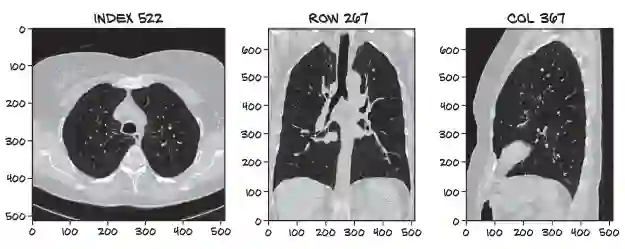

本书将带读者进入一个有趣的案例研究: 构建能够使用CT扫描检测恶性肺肿瘤的算法。 书中的作者将指导我们完成该示例,你将发现PyTorch是多么地有趣。

这本实用的书可以帮助读者从头开始构建一个真实的示例:肿瘤图像分类器。

本书的核心是设计用于癌症检测的神经网络。读者会发现训练输入有限的网络方法,并开始处理数据以获得一些结果。同时筛选出不可靠的初始结果,并将重点放在如何诊断和修复神经网络中的问题上。最后研究通过增强数据训练,改进模型体系结构以及其他微调来改善结果的方法。